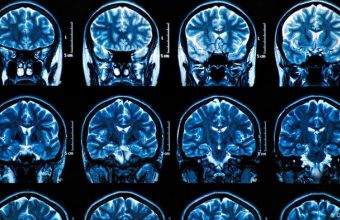

Коронавірус SARS-CoV-2 може серйозно зашкодити мозку та центральній нервовій системі, спричиняючи психози, паралічі та інсульти, що часто виявляються запізно, застерігають британські медики.

Виявилося, що новий коронавірус SARS-CoV-2 вражає не тільки легені й дихальні шляхи. Не менш серйозно він може зашкодити й іншим органам, приміром, серцю, судинам, ниркам, шкірі, а також нервовій системі. Принаймні, на це вказують дедалі більше досліджень.

Нещодавно британські неврологи ошелешили громадськість публікацією в спеціалізованому виданні Brain. Оприлюднені в ньому результати досліджень доводять, що коронавірус SARS-CoV-2 може серйозно зашкодити мозку. І таке може трапитися навіть у тих пацієнтів, у яких спостерігаються відносно слабкі симптоми, або в тих, хто вже одужав. Нерідко завдану хворобою шкоду виявляють або занадто пізно, або не виявляють взагалі.

Ось нещодавно неврологи з Університетського коледжу Лондона діагностували в більш ніж 40 британських пацієнтів гострий демієлінізуючий енцефаломієліт. Це запальне захворювання викликає дегенеративне руйнування центральної нервової системи, вражаючи мієлінові оболонки нервів головного і спинного мозку.

"COVID-19 вражає мозок у такий спосіб, який ми ніколи раніше не спостерігали в інших вірусів", - каже доктор Майкл Занді. Він є одним з провідних авторів оприлюдненого дослідження та обіймає посаду консультанта лікарень Університетського коледжу Лондона. Неприємною несподіванкою став і той факт, що серйозні пошкодження мозку можуть траплятися навіть у пацієнтів, що демонстрували легкі симптоми COVID-19.

Не виключено, що медики ще до кінця не розпізнали увесь спектр захворювань мозку та побічних явищ, які може викликати SARS-CoV-2, припускає доктор Занді. За його словами, почасти це пояснюється тим, що багато пацієнтів, які перебувають у лікарнях, занадто хворі, щоб їх можна було обстежити за допомогою сканерів мозку або іншими методами.